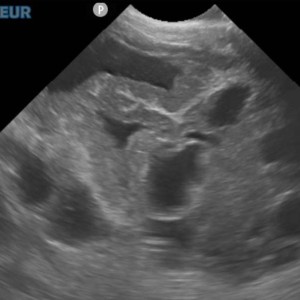

Le problème était donc bien plus grave que ce qui avait été envisagé en premier lieu. Une échographie a été réalisée avec l’aide notre confrère vétérinaire exerçant exclusivement en imagerie de « Vet&View », ce qui nous a permis d’obtenir des images de qualité permettant de poser un diagnostic de qualité : la présence de diverses masses polykystiques affectant spécifiquement le foie et une gonade.